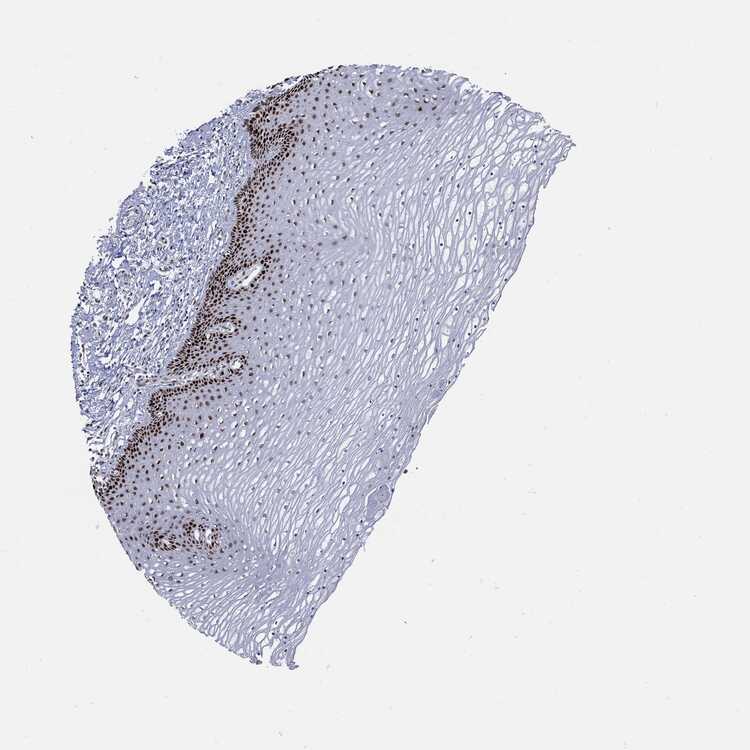

CERVIX - Antibody stainingi

Antibody staining in the annotated cell types in the current human tissue is reported as not detected, low, medium, or high, based on conventional immunohistochemistry profiling in selected tissues. This score is based on the combination of the staining intensity and fraction of stained cells.

Each image is clickable and will lead to virtual microscopy that enables deeper exploration of all samples and also displays staining intensity scores, fraction scores and subcellular localization as well as patient and tissue information for each sample.

Antibody HPA030521Antibody HPA030522Antibody HPA030523Antibody CAB000148Antibody CAB080240Antibody CAB080241Antibody CAB080242

Glandular cells LowHighNot detectedLowNot detectedMediumMedium

Squamous epithelial cells MediumHighMedium-MediumHighHigh